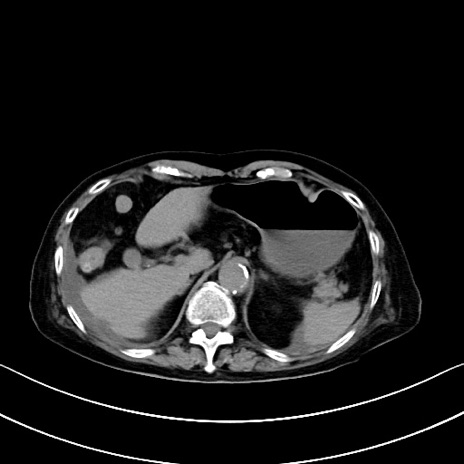

横断像

他院CT